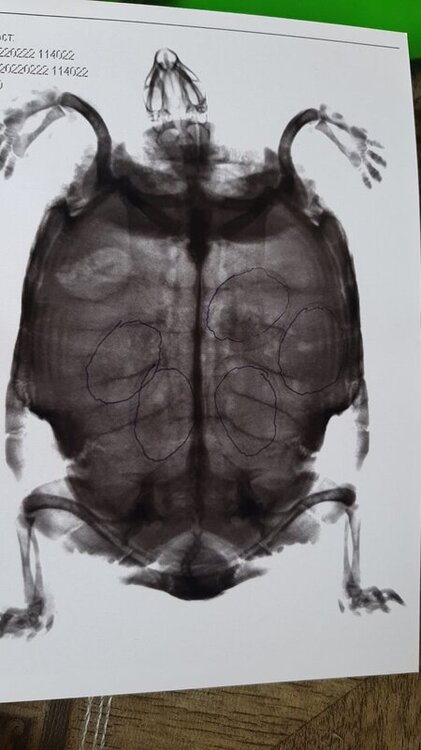

katerina.fotiadi Ваше имя: много Локация: узбекистан .коканд Опубликовано: 22 февраля 2022 Автор Опубликовано: 22 февраля 2022 9 часов назад, moth сказал: @katerina.fotiadi врач ответила 5 дней делать кальций, дальше смотреть на состояние черепахи. Если кладки так и не будет - я Вам посчитаю окситоцин, но это будет под Вашу ответственность. Сегодння звонила в Ташкентский зоопарк.сделали рентген яица с прошлого года остались .сейчас жду ответа от ветеринара с зоопарка если она скажет везти оперировать то поедем